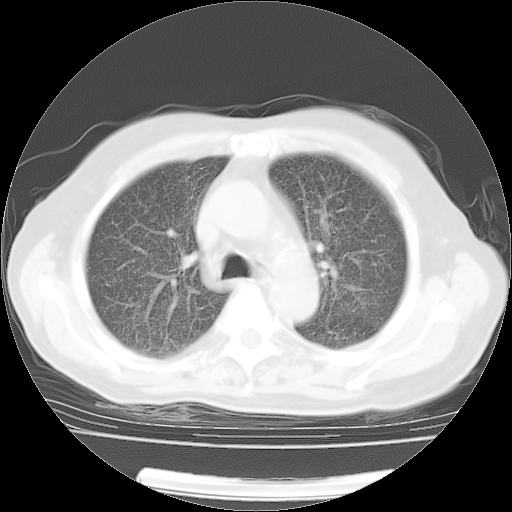

4月28日肺部CT——再次出现类似去年5月9日——透光度降低,(影像科认为)“间质性”改变。

4月28日肺部CT——再次出现类似去年5月9日——透光度降低,“间质性”改变。